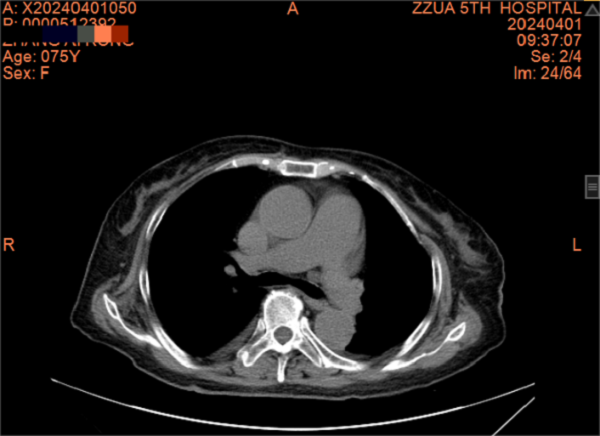

一个月前,张阿姨再发胸闷、心悸,这次张阿姨主动找到了全科医学科。住院期间因受凉出现鼻塞、流涕、发热,病情进展迅速,咳嗽、咳痰、胸闷、心悸、气喘等症状明显加重,动脉血气提示Ⅰ型呼吸衰竭并代谢性酸中毒。张阿姨精神特别差,情绪也十分低落。全科医学科主任刘培杰主任医师及别柏林主治医师综合分析病情后,第一时间给予碳青霉烯类积极抗感染、糖皮质激素抗炎、硝酸酯类扩张血管减轻心脏负荷、控制快速心室率、经鼻高流量湿化氧疗等综合治疗,护理团队给予饮食指导及心理辅导,张阿姨的病情很快得到控制,经复查胸部CT,肺部病变较前明显吸收,出院时再次对其慢性病管理及预防、治疗措施对其进行了再次的细致交代,病情好转出院。